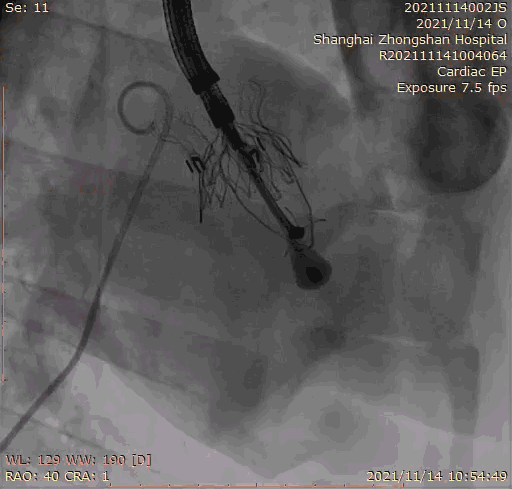

2021年11月14日星期日,復(fù)旦大學(xué)附屬中山醫(yī)院(以下簡稱中山醫(yī)院)葛均波院士團(tuán)隊(duì)成功應(yīng)用經(jīng)血管介入三尖瓣置換產(chǎn)品Lux-Valve Plus完成臨床前研究,并獲得圓滿成功!此次研究的成功預(yù)示經(jīng)血管三尖瓣產(chǎn)品Lux-Valve Plus已完成臨床前準(zhǔn)備,即將開啟后期的正式臨床研究!

上海中山醫(yī)院葛均波院士、錢菊英院長、周達(dá)新教授、潘文志教授、潘翠珍教授、李偉教授共同完成此次臨床前研究。術(shù)后葛均波院士對Lux-Valve Plus的器械操作性能給予了高度評價,DSA和超聲影像也顯示出在本次研究中Lux-Valve Plus的安全性和有效性俱佳。

本次臨床前研究經(jīng)右側(cè)頸靜脈置入LuX-Valve Plus輸送系統(tǒng)可調(diào)彎鞘管,在DSA及超聲引導(dǎo)下將人工三尖瓣瓣膜植入到原有三尖瓣位置,利用獨(dú)特的錨定技術(shù)將人工瓣膜支架可靠固定在預(yù)定的位置。